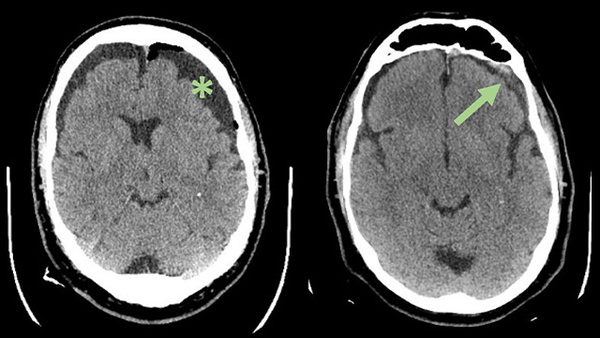

Middle meningeal artery embolization for recurrent chronic subdural hematoma

cSDH